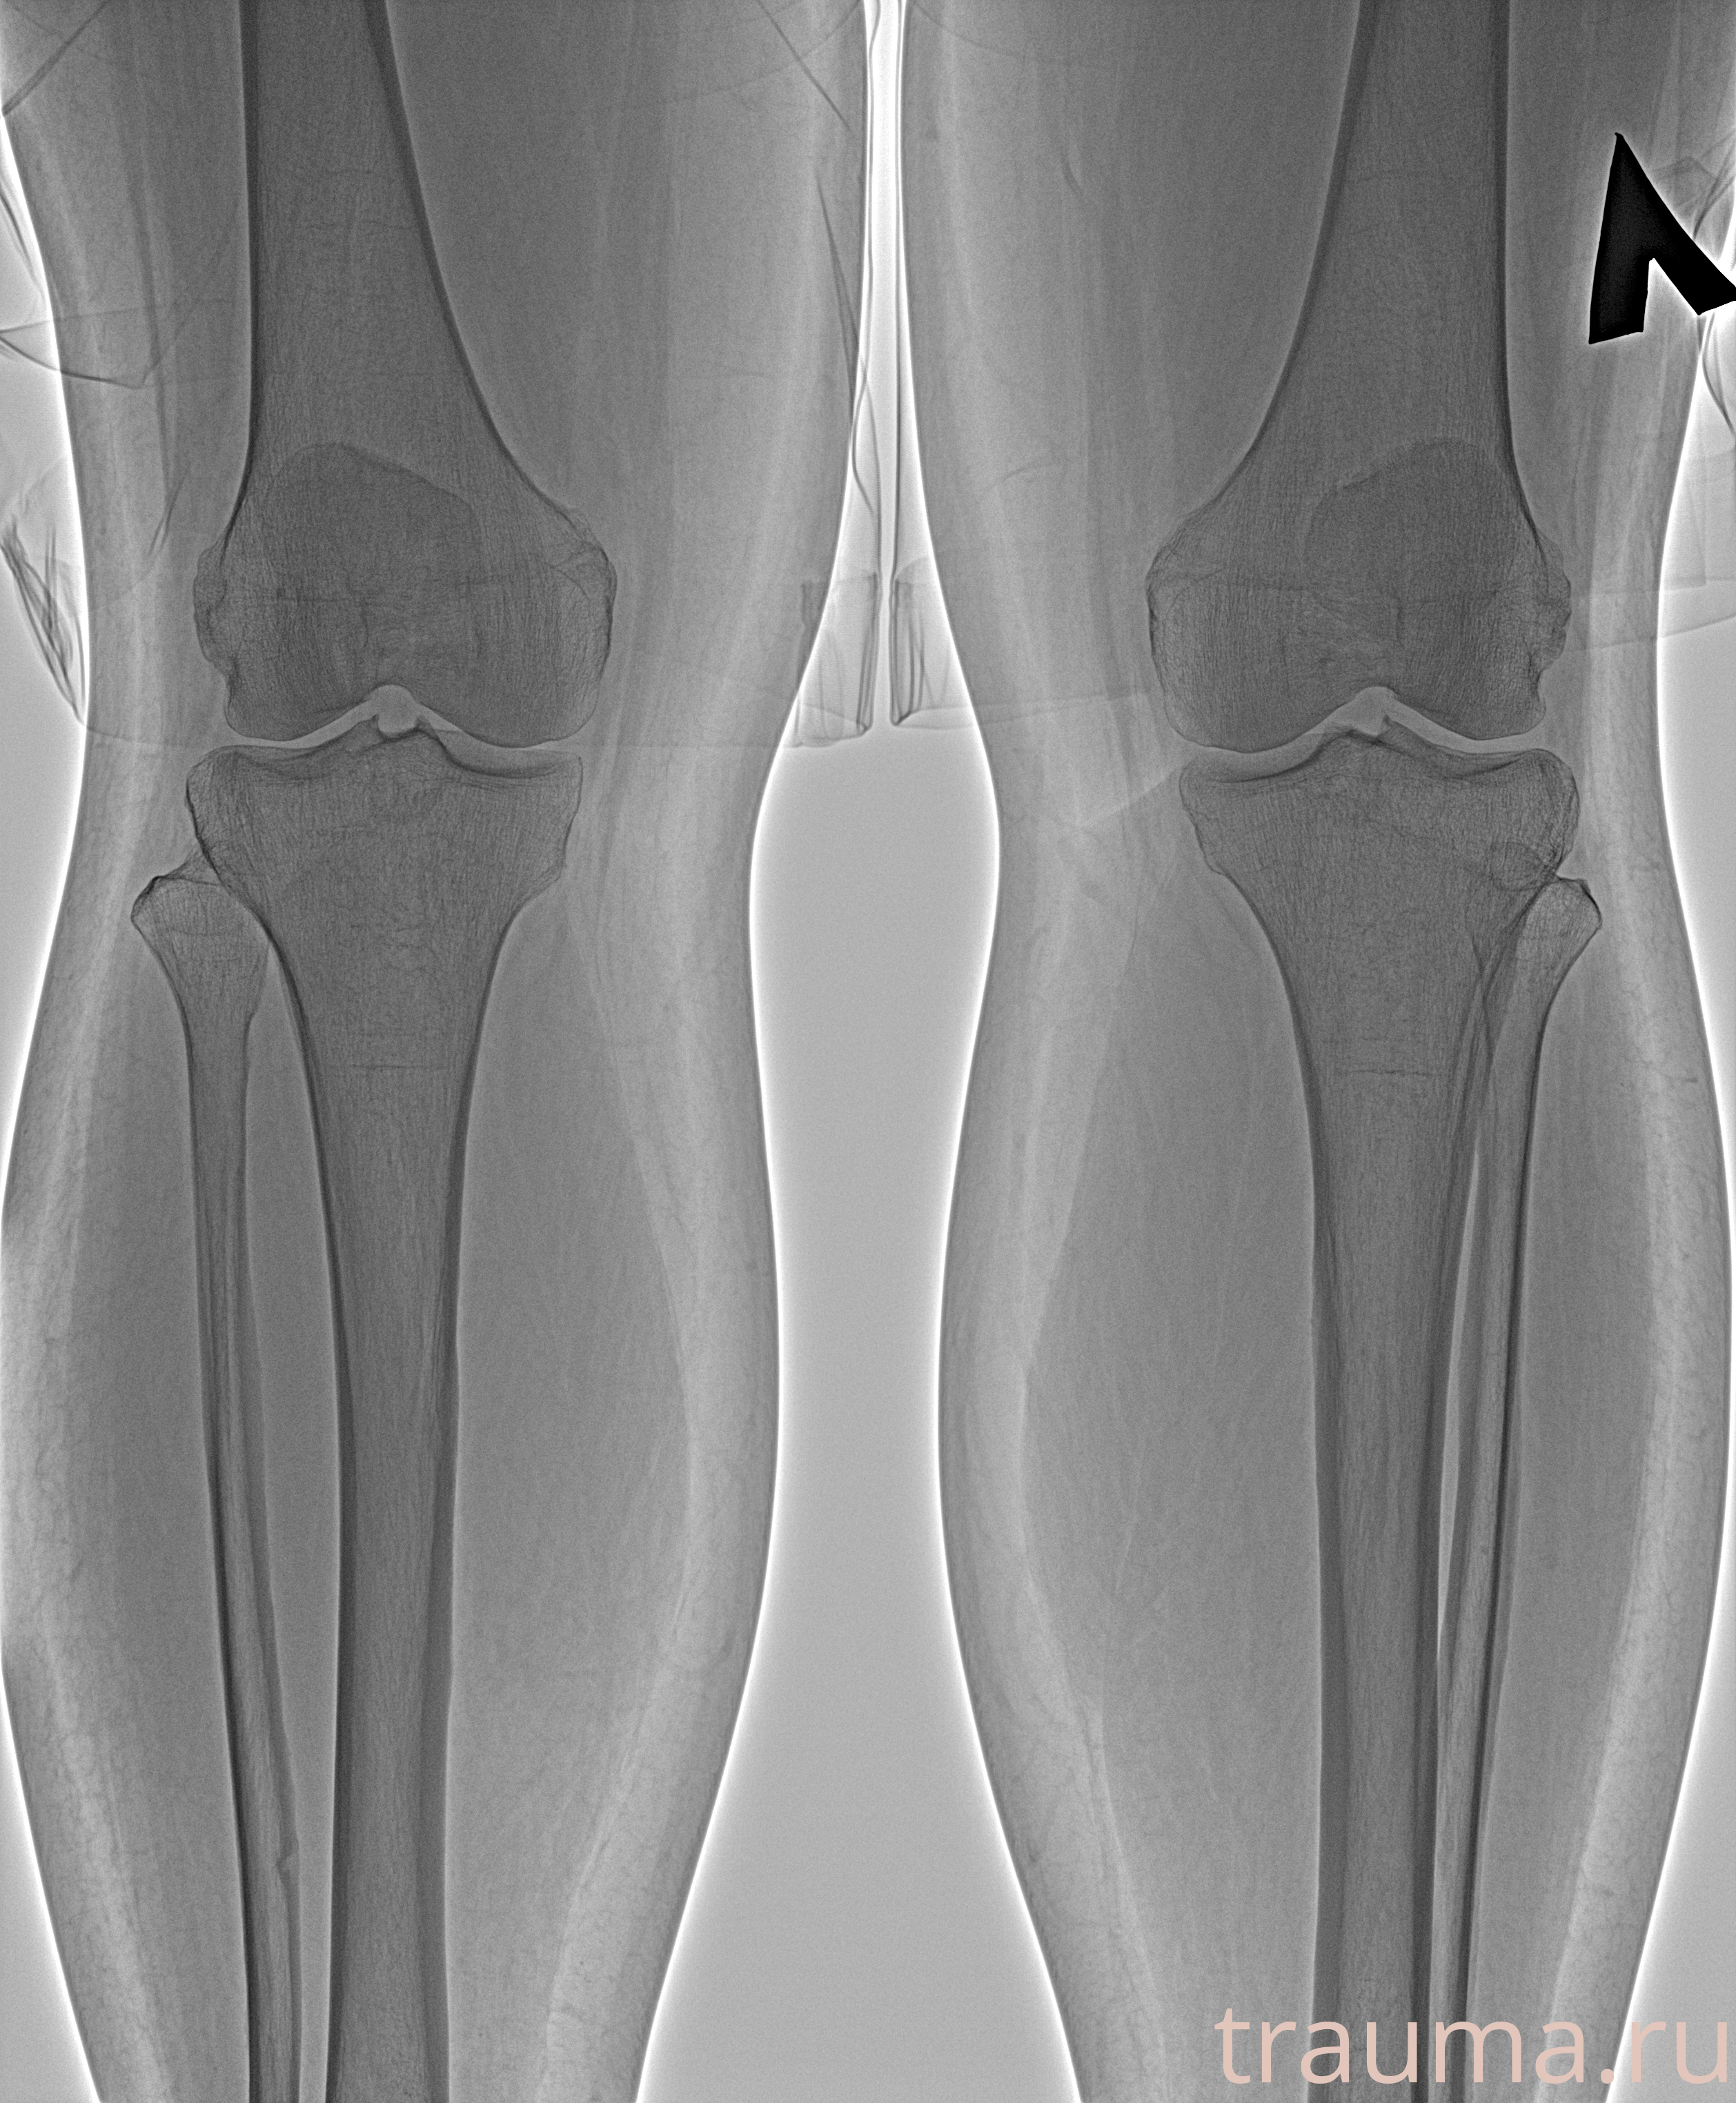

Рентген на дому: по вашему адресу приезжает врач-рентгенолог, травматолог-ортопед с мобильным рентгеновским аппаратом, проводит диагностику травмы или заболевания, делает необходимые рентгенограммы, дает рекомендации по дальнейшему лечению. Получить качественные снимки в домашних условиях возможно благодаря уникальной методике, разработанной МосРентген Центром для института  Склифосовского